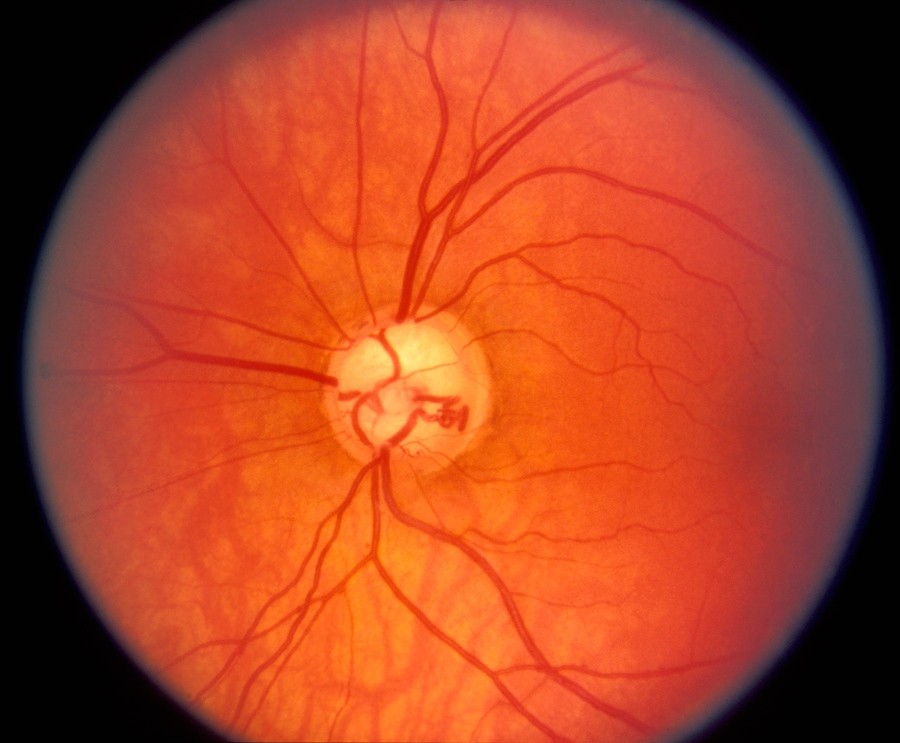

Атрофия зрительного нерва Лебера: Симптомы и лечение